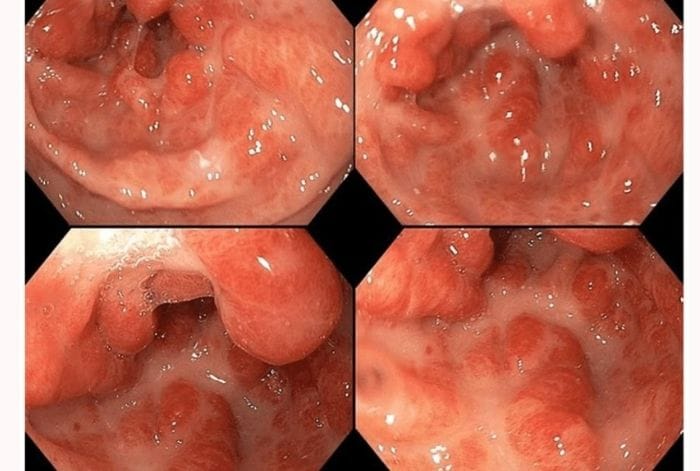

Nội soi dạ dày gây mê (hay còn gọi là nội soi không đau) là phương pháp thăm khám hệ tiêu hóa bằng ống soi mềm có gắn camera, kết hợp với việc tiêm thuốc gây mê tĩnh mạch để đưa người bệnh vào trạng thái ngủ nhẹ. Nhờ đó, người nội soi không thấy đau, buồn nôn hay khó chịu trong suốt quá trình thực hiện, đồng thời giúp bác sĩ quan sát niêm mạc rõ ràng hơn, tăng độ chính xác trong chẩn đoán và can thiệp. Đây là phương pháp an toàn, ít tai biến, hiện được áp dụng rộng rãi trong thăm khám và điều trị các bệnh lý tiêu hóa.

Nội soi dạ dày gây mê tăng độ chính xác trong chẩn đoán và can thiệp

- Chẩn đoán và can thiệp chính xác: Bác sĩ có thể tập trung quan sát kỹ lưỡng niêm mạc, phát hiện tổn thương nhỏ và thực hiện các thủ thuật cần thiết như cầm máu, cắt polyp, lấy dị vật, nong chỗ hẹp một cách an toàn, hạn chế rủi ro.